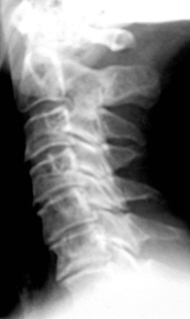

Иллюстрация 4. Определяется выраженная «выпрямленность» шейного лордоза. Имеет место скошенность передне-верхних лимбусов тел С3, С4, С5, С6. Определяется некоторое снижение высоты тела С 5 в передних отделах. В дугоотросчатых суставах определяется субхондральный склероз, неровность замыкательных пластинок.